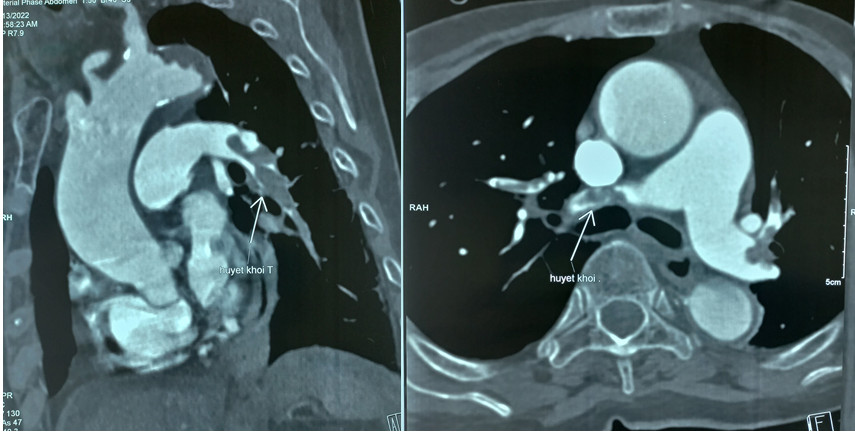

Bệnh nhân N.T.T. (92 tuổi), vào viện vì gãy xương đùi phải có chỉ định thay khớp háng. Trong quá trình phẫu thuật đột ngột tụt huyết áp, nhịp tim chậm dần, các bác sĩ nhanh chóng nghĩ ngay đến hiện tượng thuyên tắc động mạch phổi và chụp CT động mạch phổi.

Bệnh nhân N.T.T. 92 tuổi sốc tim do thuyên tắc động mạch phổi cấp hai bên.

Bệnh nhân được dùng thuốc tiêu sợi huyết cấp cứu ngay trên bàn phẫu thuật, kết hợp hồi sức tim mạch tích cực trước, trong và sau mổ. Tình trạng của bà sau khi được chẩn đoán và điều trị kịp thời tiến triển tốt lên theo từng giờ. Hiện tại bà đã tỉnh táo và có thể tự sinh hoạt bình thường.